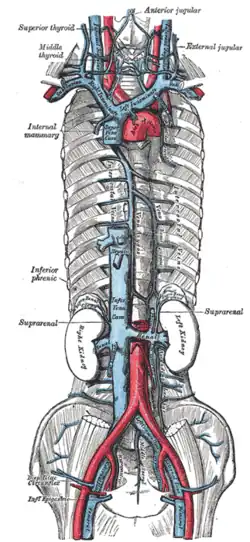

Blood supply

Arteries and veins above and below the diaphragm supply and drain blood.

From above, the diaphragm receives blood from branches of the internal thoracic arteries, namely the pericardiacophrenic artery and musculophrenic artery; from the superior phrenic arteries, which arise directly from the thoracic aorta; and from the lower internal intercostal arteries. From below, the inferior phrenic arteries supply the diaphragm.[7]

The diaphragm drains blood into the brachiocephalic veins, azygos veins, and veins that drain into the inferior vena cava and left suprarenal vein.[7]